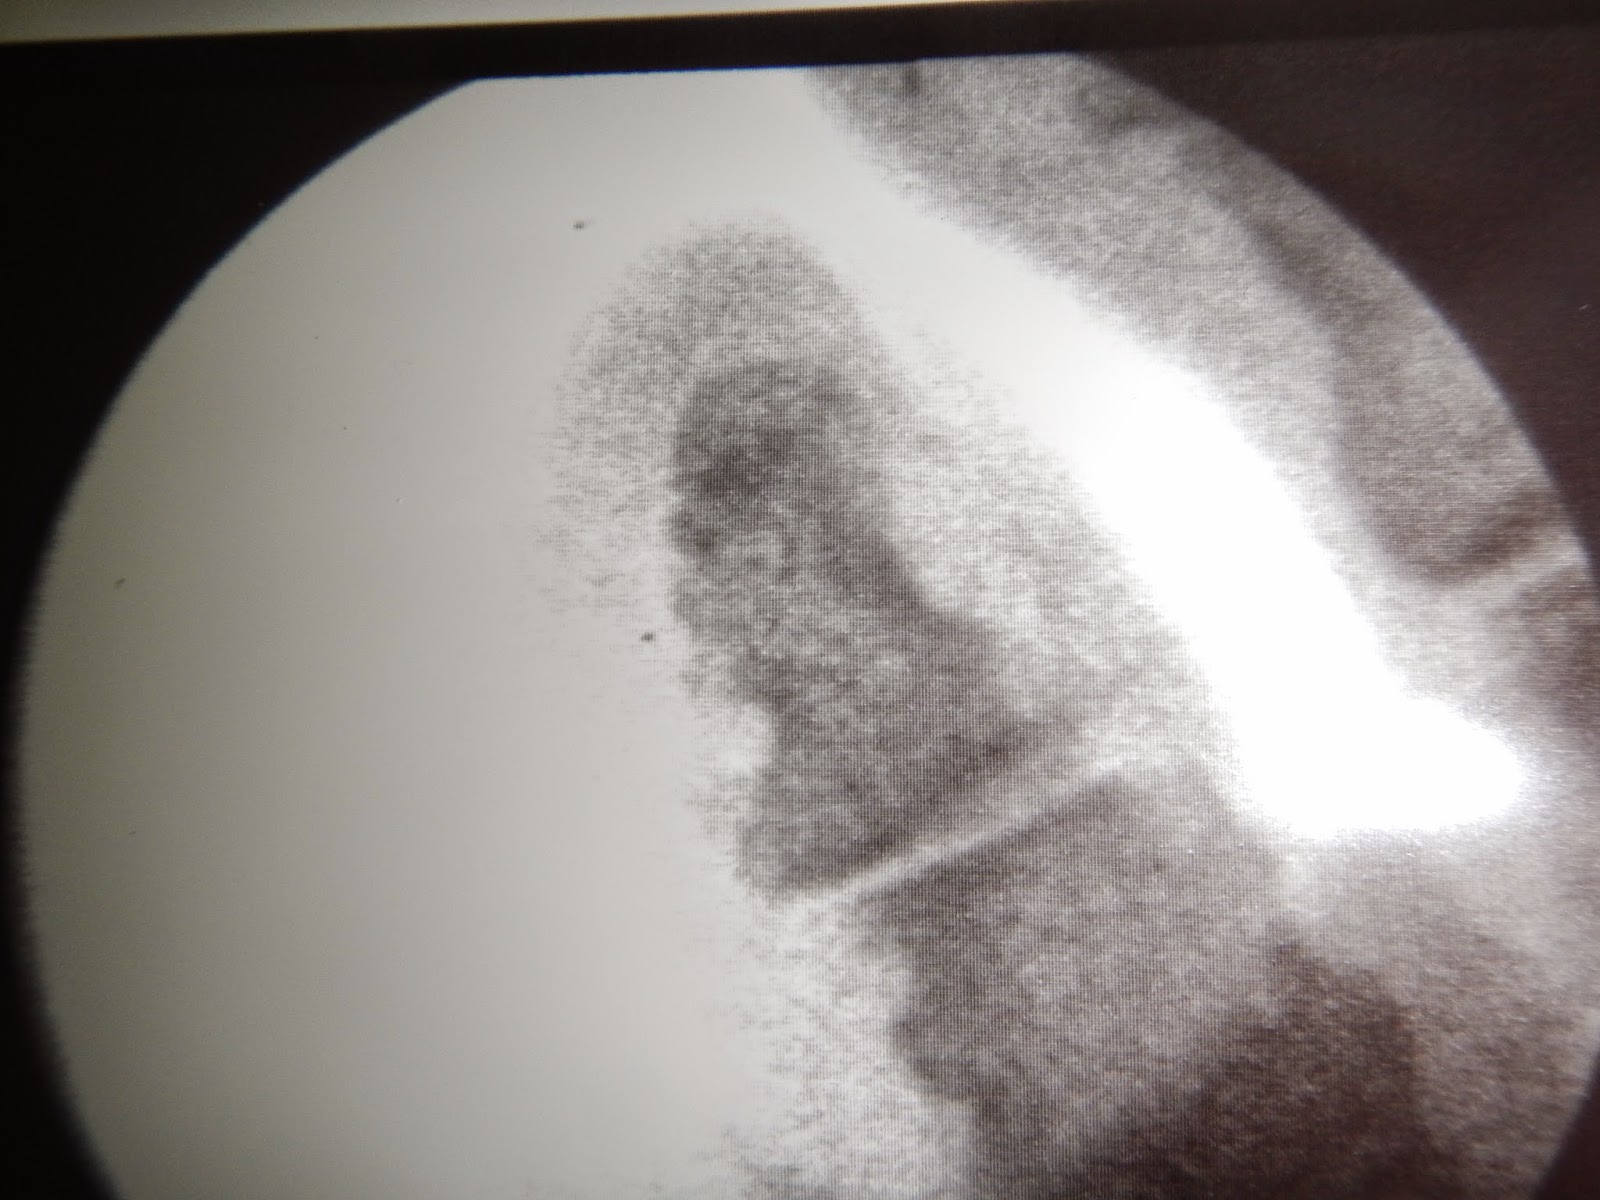

Nos ayudamos con el fluoroscopio para ver que realmente estamos fresando lo que queremos.

Podemos ver que estamos fresando el cóndilo de la falange.

Después de haber fresado, comprobamos como ha quedado la zona, también en imagen fluoroscópica.

Placa preoperatoria donde vemos el cóndilo responsable del heloma.

Placa post operatoria aumentada donde vemos que hemos retirado el cóndilo.